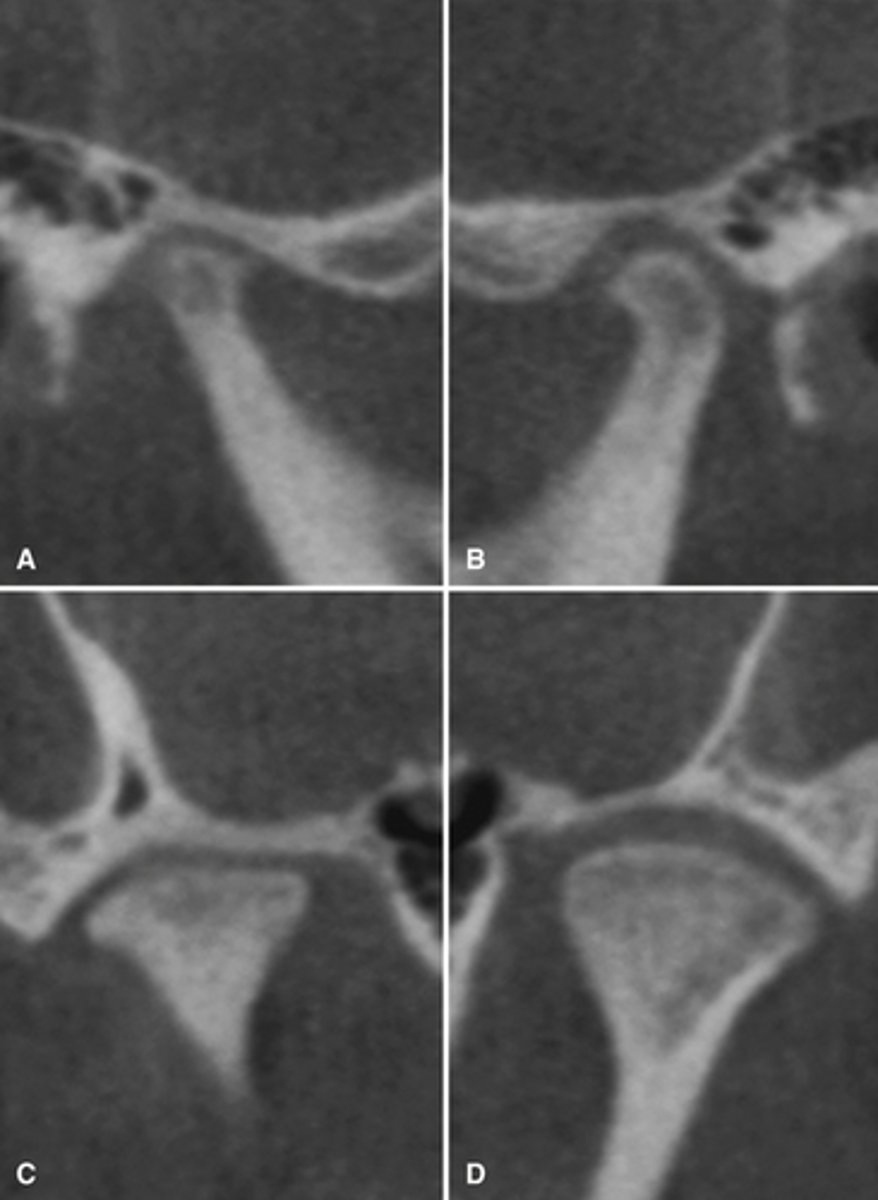

The bottom radiographs depict a developing 7year-old child.

1. The cortication of all the articulating surfaces are thin.

2. The mandibular fossa is shallow

3. The articular eminence is short

The top images are being compared to the bottom images, which patient is younger and what are all the ways to know this.